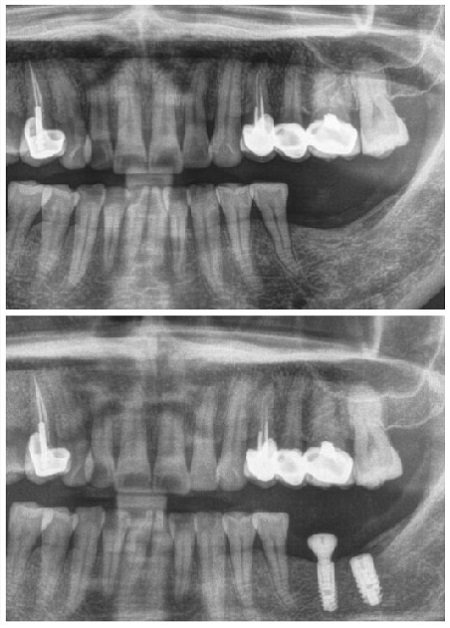

李大姐种植牙前后拍片对比图

为李大姐实施种植牙手术的是口腔科周斌主任。经过前期的口腔全景及颌骨CT检查、种植体植入、基台愈合等环节后,周斌主任开始正式对李大姐实施种植牙手术,两颗为李大姐“量身订做”的德国ANKYLOS种植牙被成功植入牙槽骨内。五十分钟后,种植牙植入完成了!

种植术后,李大姐的恢复情况良好,曲面断层片显示种植牙根完美植入了缺失牙位。看着这两颗“新长”的牙齿,李大姐笑着说她终于可以摆脱缺牙的困扰了。